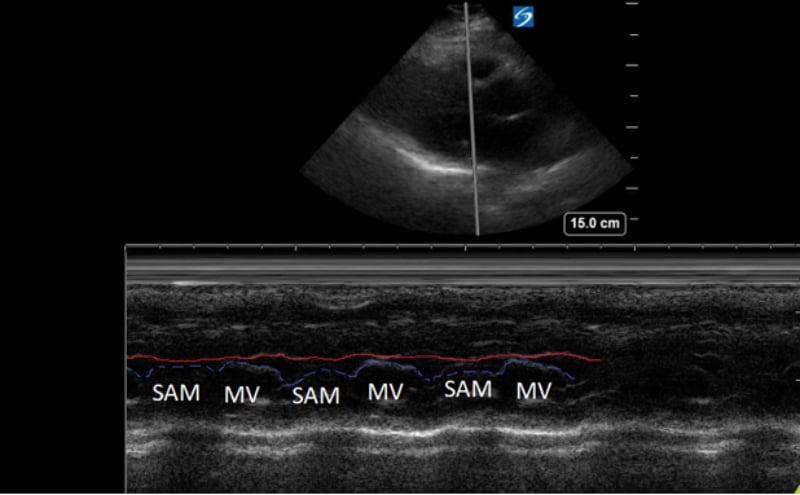

A point-of-care ultrasound was performed to evaluate for potential etiologies of syncope. The ultrasound displayed biventricular and interventricular septal hypertrophy (Figure 2), systolic anterior motion of the mitral valve (SAM, Figure 3), and a “dagger-like” continuous wave Doppler waveform emerging from the left ventricular outflow tract. (LVOT, Figure 4)

Figure 3. Parasternal long-axis view using M-Mode displaying SAM of the mitral valve against the interventricular septum (red line). Note how the mitral valve shifts anteriorly during the same period that the septum contracts posteriorly.

Hypertrophic obstructive cardiomyopathy (HOCM) refers to the common obstructive subset that affects 70% of patients with HCM.6 Left ventricular outflow tract obstruction (LVOTO) has been shown to be an independent predictor for adverse outcomes by multiple studies.7 Traditionally, systolic anterior motion (SAM) of the mitral valve was thought to be pathognomonic for HCM. Recent studies have shown that of the HCM patients with SAM, 25-50% will have LVOTO.8 Using ultrasound, SAM is observed in the parasternal long-axis using M-mode over the anterior leaflet of the mitral valve. The time the valve is contact with the septum quantifies disease severity.

1) Mild: brief SAM without septal contact

2) Moderate: septal contact < 1/3 of systolic period

3) Severe: septal contact > 1/3 of systolic period9